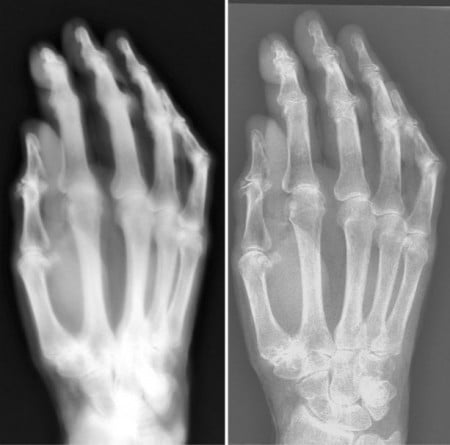

A comparison of an X-ray of a hand using 1896 technology (left) and a modern digital radiography X-ray system.

The researchers compared the radiation dose, X-ray beam properties and electrical characteristics of the 1896 system with those from a modern X-ray system. Using the same exposure conditions used in 1896, the estimated skin dose needed to image the hand was nearly 1,500 times greater on the first-generation system than on the modern system — 74 milligrays (mGy) and 0.05 mGy, respectively. Corresponding exposure times were 90 minutes for the old system and 21 milliseconds for the modern system.

Pinhole images showed the X-rays originated from an extended area of the glass wall in the system’s construction, causing image blurring. Still, the 114-year-old system produced what Kemerink described as surprisingly good images in which anatomical details were clearly visible.